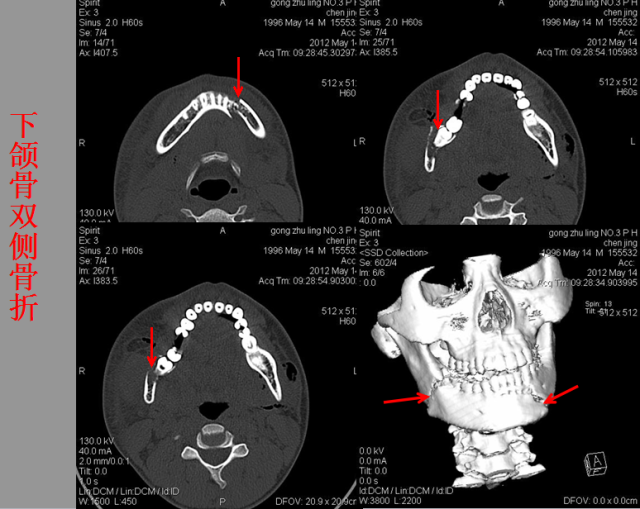

骨折篇

01

定义:骨折{Fracture}是指骨的完整性和连续性的折裂或粉碎。包括创伤性骨折、疲劳性骨折和病例理性骨折。 临床上以创伤性骨折*常见。